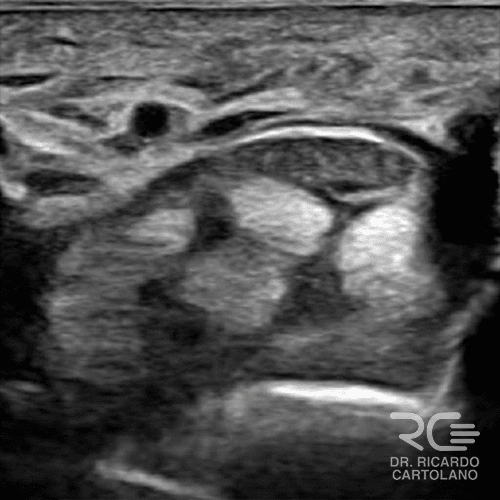

Ultrassonografia

Um exame dinâmico e ágil. Permite avaliar tendões, ligamentos e cistos em tempo real, inclusive com a mão em movimento. Ótimo para guiar infiltrações e diagnosticar inflamações.